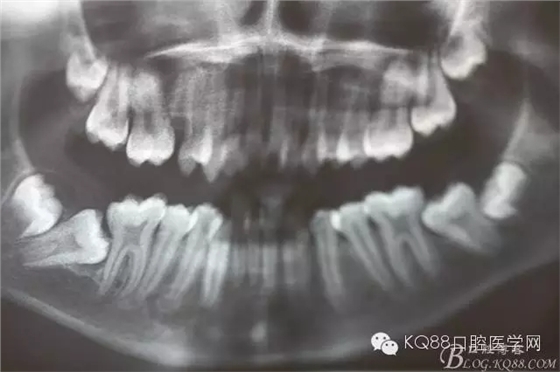

圖3. 這是患者的全景片影像檢查:看不清16與14之間是否有牙根遺留